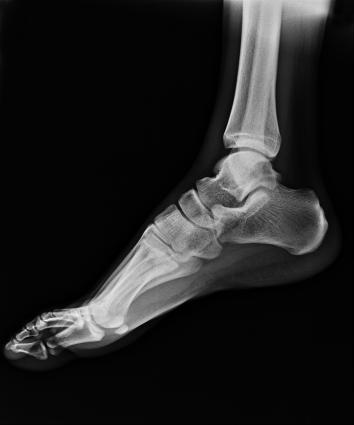

電動旋轉內平衡結構,可實現(xiàn)快捷擺位,滿足特殊體位的靜態(tài)與動態(tài)檢查。